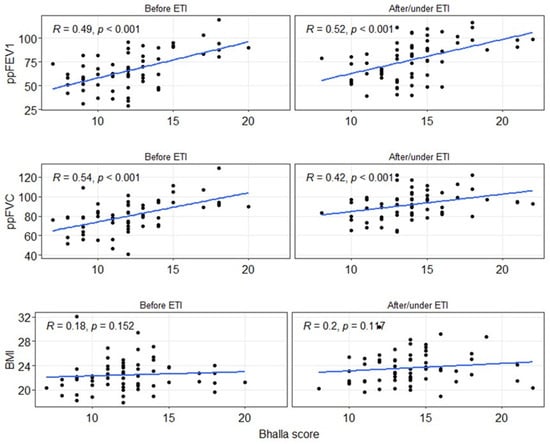

To assess the impact of ETI on lung function and BMI, correlation analyses were conducted between the Bhalla score, spirometry values, or BMI, both before and after ETI (Figure 3). A moderate and significant correlation (p < 0.001) was observed for the spirometry values, while no significant correlation (p > 0.05) was found for BMI. Regarding the ppFEV1 value, the correlation slightly increased after ETI (Rho = 0.49 to 0.52), although it remained within the moderate correlation range. In contrast, the correlation for ppFVC decreased (Rho = 0.54 to 0.42), but still remained within the moderate correlation range.

Figure 3.

Spearman correlation between the global Bhalla score, spirometry measurements (ppFEV1 and ppFVC), or BMI before and after/under ETI treatment. BMI: body mass index. ETI: elexacaftor–tezacaftor–ivacaftor. ppFEV1: percentage of predicted forced expiratory volume in the first second. ppFVC: percentage of predicted forced vital capacity.